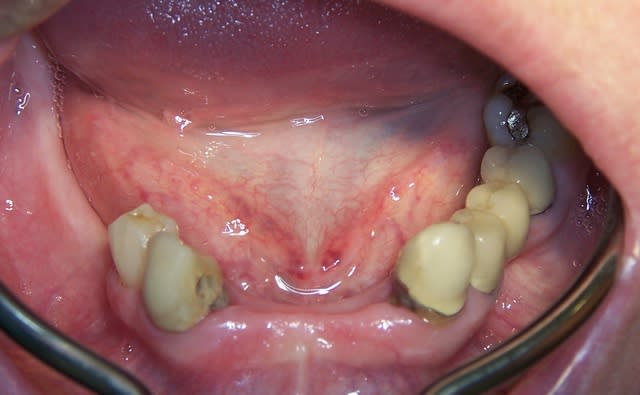

Jeune homme, 20 ans, accident de vélo.

Perte de 11 et 21.

Arrive dans mon cabinet 8 jours post trauma.

J'ai placer sous antibio et 2 jours après j'ai curetté les alvéoles, fait lambeau (perte de paroie buccale), placer 2 4,6 X 15 mm en palatin, greffe MINEROS, membranne (suturée sous le lambeau palatin + 2 tacs en titane au buccal).

Extension du lambeau au buccal et fermeture.

Ah oui, freinectomie laser en mêm temps, histoire de s'occuper un peu. Pas de temporisation sur implants avec une perte d'os au buccal. Prothèse acrylique amovible de transition, placée 7 jours post-op.

La 2e photo est 7 jours post-op, la sem dernière.

Zéro enflure, zéro douleur, pas d'anelgésique.